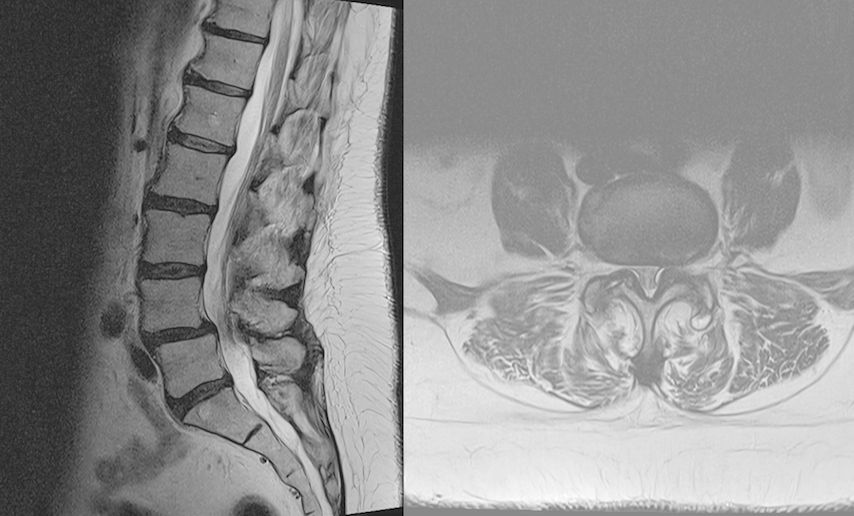

TLIF über Mittellinienzugang mit Schrauben in „cortical bone trajectory“. Bei der 63-jährigen Patientin bestand eine degenerative Spondylolisthese Meyerding Grad I mit Facettengelenkszysten und Wirbelkanalstenose (Abb. 8). Klinisch bestanden Lumboischialgien mit Ausstrahlung dem Dermatom L5 bds. entsprechend. Es wurde ein Mittellinienzugang durchgeführt und zuerst wurden navigierte Schrauben in „cortical bone trajectory“ platziert (Abb. 9). Anschließend erfolgten eine Facettektomie L4/5 links und eine Dekompression des Wirbelkanals. Abbildung 10 zeigt, dass der Hautschnitt aufgrund der mittelliniennahen Schraubenköpfe klein gehalten werden kann. Klinisch wurden die lumbalen Schmerzen wie ausstrahlende Beschwerden 1 Jahr postoperativ annähernd vollständig behoben, die korrespondierende Röntgenkontrolle ist in Abbildung 11 dargestellt.

Die Navigation stellt nicht nur beim Einbringen von Implantaten eine Hilfe dar, sondern kann auch in anatomisch herausfordernden Situationen rein zur Verbesserung der Orientierung zu Hilfe genommen werden. Mögliche Anwendungsfelder stellen hier beispielsweise die untere HWS oder der zervikothorakale Übergang dar, welche im konventionellen Röntgen teilweise schwer darstellbar sind. Abbildung 16 zeigt den MR-Befund einer 32-jährigen Patientin, die auswärtig zur ACDF C6/7 indiziert wurde, wobei der Eingriff dort aber aufgrund der Unmöglichkeit, die HWS unter Durchleuchtung entsprechend einzustellen, nicht erfolgte. Abbildung 17 zeigt das intraoperative Röntgen mit bereits kräftigem Schulterzug, in dem aber nur mehr das Segment C4/5 sicher beurteilt werden kann. In diesem Fall erfolgte mittels O-Arm der Eingriff navigiert. Ein anderes Beispiel ist die Anwendung zur Orientierung bei Osteotomien, wo die Navigation an unserer Klinik ebenfalls standardmäßig angewendet wird. Abbildung 18 zeigt einen intraoperativen Screenshot im Rahmen der Navigationsanwendung bei einer thorakalen Corporektomie (Th12) von dorsal im Rahmen einer Tumorresektion. Auch bei verkalkten Bandscheibenvorfällen, wie in Abbildung 19 dargestellt, kann die Navigation zur besseren intraoperativen Orientierung herangezogen werden. Ein weiteres Beispiel der vielfältigen Anwendungsmöglichkeiten der Navigation zeigt Abbildung 20. In diesem Fall wurde im Rahmen einer C1/2-Verschraubung nach Harms das Gelenk C1/2 beidseits navigiert zur besseren Fusion angefrischt.